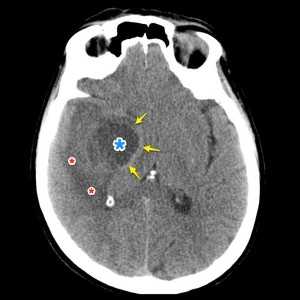

Опухоль головного мозга — глиобластома. Компьютерная томография (КТ). Синяя звездочка в центре обозначает зону центрального некроза опухоли, заполненную жидкостью. Желтые стрелки — окружающий мягкотканный компонент опухоли. Красные звездочки — перифокальный отек мозга. Наблюдается смещение срединных структур и угроза нисходящего транстенториального вклинения мозга.